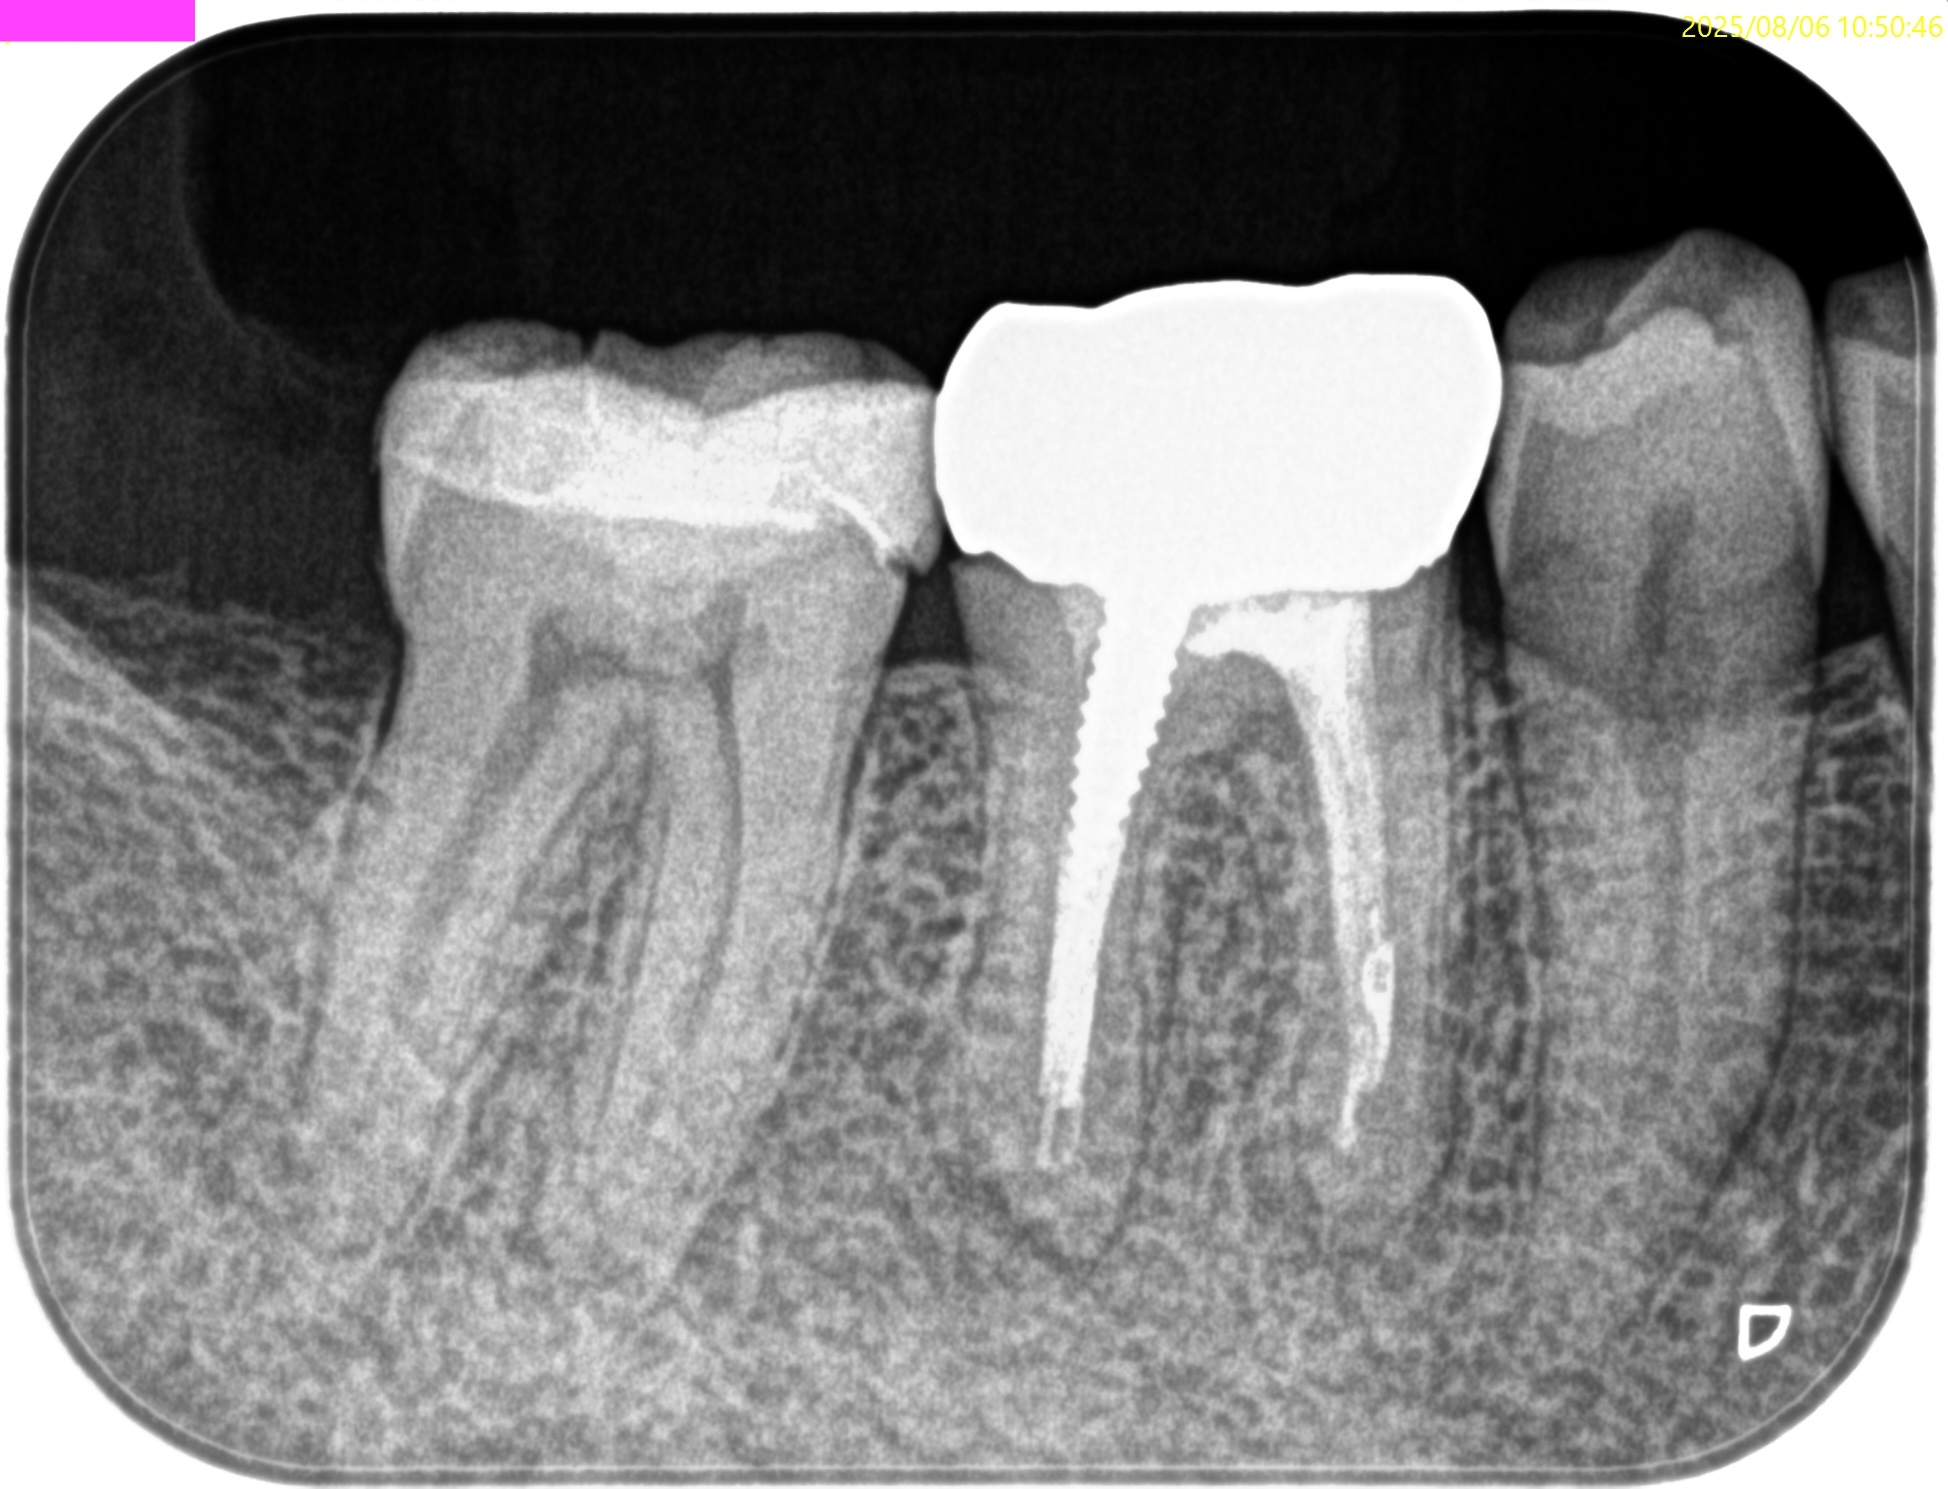

PA(2025.8.6)

#30には不完全な根管治療が、

#31には歯髄に近接する生活歯髄療法がなされている。

臨床症状から考えると、それぞれ根管治療が必要だろう。